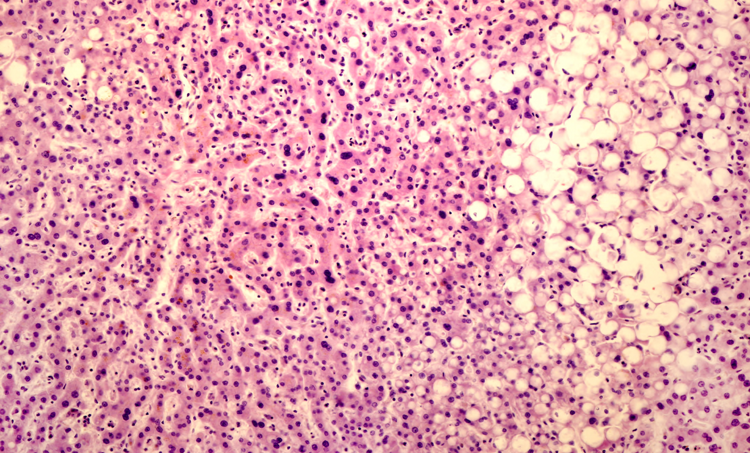

Voeding en leefstijl bij de non-alcoholisch vervette lever